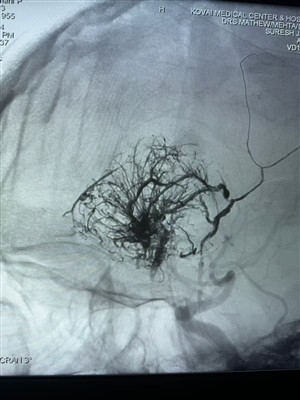

Primer caso de tumor hipervascular informado en la IndiaFeliz de compartir este primer caso de tumor hipervascular realizado en la India. Fue tratado con Lava Liquid Embolic System de NeuroSafe Medical Co., Ltd. Gracias al Dr. Mathew Cherian. Fue pioner...